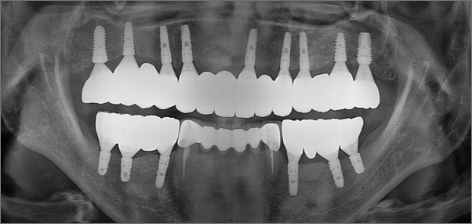

초진 : 2014.01.18

치료 후 : 2015.11.17

10년 후 : 2024.02.03

치료 기간 : 2014.01.18 ~ 2024.02.03

THE 이해승치과에서 2014년 치료 받으신 40대 환자분의 사례입니다. 흡연과 음주가 근본 원인이 되어 2014년 전악 임플란트 치료를 받으셨습니다. 감사하게도 저희와 함께 꾸준히 10년 관리를 동행해오시면서 추가적인 전신 질환 없이 건강한 50대를 보내고 계십니다. 치료 경험을 통해 변화를 만드신 환자분을 존경합니다.